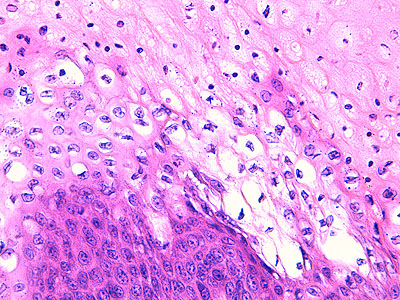

Photo 6 (Hémalun Eosine X 400) : vue rapprochée au fort grossissement d’une crête épithéliale

émanant de la gaine épithéliale externe d’un follicule pileux (portion infundibulaire).

L’aspect filiforme et longiligne s’accompagne d’une certaine perte de polarité des cellules basales

dont le grand axe cytoplasmique devient parallèle au grand axe de la crête épithéliale, au lieu

d’être perpendiculaire. La couche la plus basale perd ainsi son habituel aspect palissadique.

Légendes de la Photo 6 :

- Triangles bleus clairs : contours de crêtes épithéliales allongées, filiformes, ramifiées et branchues, peuplées de cellules basales hyperbasophiles, émanant de la gaine épithéliale externe des infundibula folliculaires

- Flèches rouge : parakératose folliculaire

- Étoiles rouge pleines : Le derme est faiblement à modérément inflammatoire (infiltrat mononucléé)

- Étoiles rouges claires : angiectasie des capillaires sanguins

- Ronds marron :tiges pilaires

- Flèches orange : mélanocytes

- Flèches jaune : mélanophages